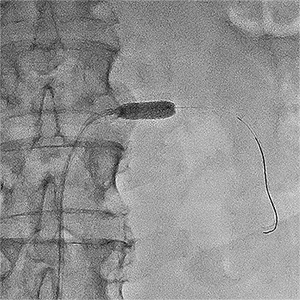

Приклади ангіограм до та після дилятації:

стеноз лівої клубової артерії    балон, роздутий в зоні стенозу    відновлення отвору клубової артерії

Значний стеноз лівої

наружної клубової артерії

Балон-катетер,

роздутий в зоні стенозу

Отвір артерії відновлено на 80%